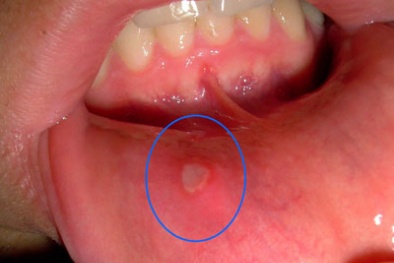

Cẩn trọng với những thực phẩm gây nhiệt miệng

(VietQ.vn) - Ăn những thực phẩm nóng, cay, chứa chất kích thích hay axit là một trong những nguyên nhân phổ biến cần được lưu ý để có thể bảo vệ bản thân khỏi bệnh nhiệt miệng, tuy không nguy hiểm nhưng lại cực kỳ khó chịu và đau đớn này.

Những loại thuốc trị nhiệt miệng hiệu quả hiện nay

(VietQ.vn) - Có đến 20% dân số bị nhiệt miệng. Tuy không phải là bệnh nặng nhưng nó làm người bệnh đau đớn, dễ tái phát gây cản trở ăn uống và sinh hoạt.